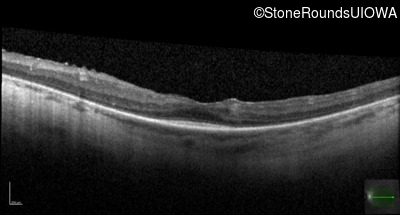

Optical Coherence Tomography - Left - 20/50 -2

Exemplar / OCT Stack